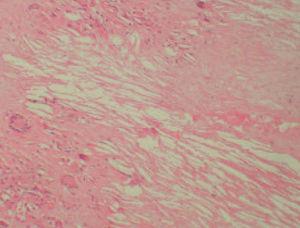

Se realizó una biopsia de una de las lesiones y el estudio histopatológico mostró, bajo una epidermis ligeramente adelgazada, un infiltrado granulomatoso que ocupaba la dermis y el tejido subcutáneo. Se apreciaban, entre los focos granulomatosos, zonas de necrosis hialina y espacios claros aciculares que sugerían la presencia de cristales de colesterol (fig. 3). Los granulomas estaban formados por histiocitos, células espumosas y células gigantes multinucleadas tipo Langhans y tipo cuerpo extraño (fig. 4). Se realizaron tinciones para lisozima y CD-68 que fueron positivas en las células histiocíticas. Todos los cultivos realizados para micobacterias y hongos fueron negativos.

Fig. 3.—Infiltrado localizado en dermis en el que se aprecia necrobiosis y la presencia en la misma de unos espacios claros (espacios claros aciculares de colesterol). (Hematoxilina-eosina, ×100.)

Las alteraciones histopatológicas cutáneas se localizan principalmente en la dermis reticular e hipodermis, respetando la epidermis y la dermis papilar. Se presentan amplias zonas de necrosis hialina asociada a granulomas «en empalizada», compuestos por células espumosas, histiocitos, folículos linfoides y células gigantes que pueden ser aberrantes, a cuerpo extraño o tipo Touton. En las zonas de necrobiosis se pueden apreciar, hasta en un tercio de los casos, espacios claros aciculares que se corresponden con depósitos de colesterol1-3. Se ha encontrado infiltración histológica de otros órganos por los xantogranulomas1,2,4,5, lo que demuestra que el xantogranuloma necrobiótico es una enfermedad sistémica con afectación cutánea. Las lesiones cutáneas han sido bien caracterizadas en la literatura médica, pero hay poco descrito sobre la afectación sistémica4. Se han encontrado lesiones en laringe, pulmón, corazón, sistema reticuloendotelial y ojos. En el caso de la afectación cardíaca se han visto afectados el pericardio y miocardio. Los diagnósticos definitivos se realizaron post mortem y no hubo previamente ninguna prueba de imagen, por lo que algunos autores recomiendan realizar ecocardiografía y pruebas de imagen cardíacas dinámicas a los pacientes con xantogranuloma necrobiótico3,4.